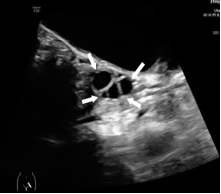

发育的卵巢,可见多个直径≥4 mm 的卵泡

(白色箭头所指)